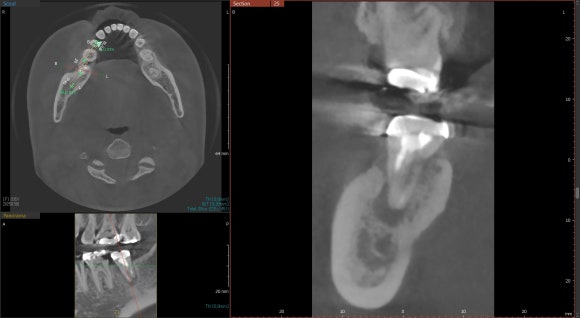

20250106

30대 여성 환자분입니다.

전반적으로 구강위생이나 치아건강이 양호하신 편이십니다.

오른쪽 아래 어금니를 보겠습니다.

뿌리 끝을 감싸고 있는

검은 공간이 보이실겁니다.

치근단염증이라고도 합니다.

신경치료 후 염증이 재발되어

뿌리 끝에 매달려있는 것이지요.

치료 받으신지 오래되셨고,

예전의 치료가 아주 부족해보이진 않습니다.